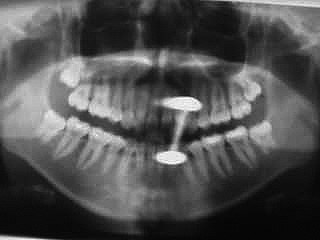

bitte alle metallischen Gegenstände vorher entfernen Halskette, Zahnprothese, Ohr Nasen etc. Ringe - Bild:Zungenpiercing verdeckt Zähne im Röntgenbild.

Warum raten wenn es doch moderne digitale Röntgenverfahren gibt mit denen man ohne körperliche Maßnahmen von außen alles durchleuchten und erkennen kann. Röntgenbilder wirken also vorbeugend. Sie sollen Fehlbehandlungen vermeiden und am besten noch bevor es schmerzt Probleme aufzeigen. Auf Grund ständiger Verbesserungen konnte die Strahlenbelastung dermaßen reduziert werden, dass bei einem Röntgenbild weniger Strahlung aufgenommen wird als vergleichsweise bei einem Jet - Flug in 8000 m Höhe. Vor jeder Zahnersatzplanung muss über ein aktuelles Röntgenbild herausgefunden werden ob ausreichend Zahnsubstanz und Knochen für den geplanten Zahnersatz vorhanden ist. Bitte denken sie mit: vor dem Röntgen sollten alle metallischen Gegenstände im Strahlenbereich entfernt werden . Dazu gehören Halsketten Ohr und Nasenringe und wie in diesem Fall ein Zungenpiercing Ausnahmefälle (Zungenpiercing konnte nicht entfernt werden) bitte vorher mit dem Behandler absprechen. Röntgenbilder helfen dabei : Die Schmerzursache zu finden Eiter im Knochen zu finden. Die Länge von Wurzeln bei der Wurzelbehandlung zu bestimmen. Karies zu entdecken, bevor es weh tut, auch unter Füllungen und Kronen Wurzelreste oder versteckte Weisheitszähne im Knochen zu finden.